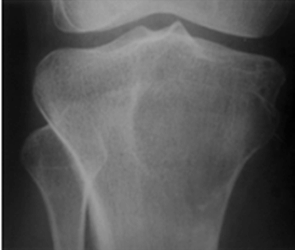

Fig 120. Tumor de células gigantes.

Rx AP. Imagen excéntrica, lítica y parcialmente definida, en la metáfisis tibial, por tumor de células gigantes.

Fig 121. Tumor de células gigantes.

TAC reconstrucción coronal. Imagen expansiva y lítica, en el alerón del sacro, sin ruptura de la cortical, por tumor de células gigantes.